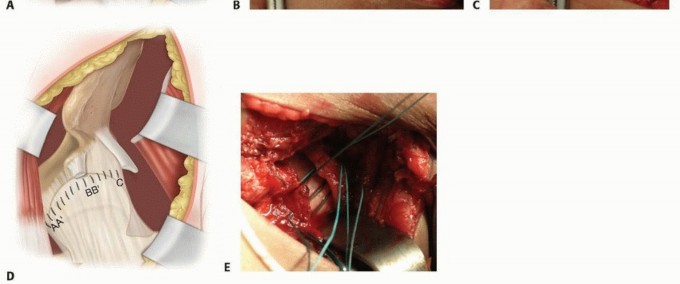

A T-shaped capsulorrhaphy is made with the redundant proximal limb eventually removed.

The incision parallels the acetabular rim but is about a centimeter away so that the labrum is not injured (

TECH FIG 2A

).

The femoral head is examined for deformity (

TECH FIG 2B

The ligamentum teres is divided off the femoral head (

TECH FIG 2C

The stump of the ligamentum teres is grabbed with a Kocher clamp and it is followed into the depths of the acetabulum.

It is essential to visualize the entire acetabulum and the transverse acetabular ligament.

The ligamentum teres is removed with Mayo or cartilage scissors at its deep acetabular attachment.

Under direct vision, a pituitary rongeur is used to remove the pulvinar tissue that lies within the acetabulum.

The transverse acetabular ligament is divided. At this point, the femoral head should be reducible.

For children older than 2 to 3 years of age, especially if the reduction is tight or unstable, a femoral shortening osteotomy is performed before the capsule is closed.9

If an acetabular osteotomy is performed, it is also completed before the capsulorrhaphy sutures are tied.

An adductor longus and gracilis tenotomy is generally not needed but can be included if these muscles feel excessively tight.

TECH FIG 2 • A. A T-shaped capsulorrhaphy is performed. The upper limb is generally excised. B. The hip capsule has been opened, exposing the deformed femoral head. C. The ligamentum teres is divided off its femoral head attachment. The vascular contribution of the ligamentum teres to the femoral head is minimal. D. After any associated femoral and acetabular osteotomies are performed, the capsule is advanced medially. E. Nonabsorbable sutures are placed and tied after osteotomies have been completed. A capsulorrhaphy is performed by advancing the superolateral capsule to the inferior medial aspect of the capsule on the pubis (

TECH FIG 2D

Nonabsorbable no. 0 sutures are all placed and tagged and then sequentially tied (

TECH FIG 2E